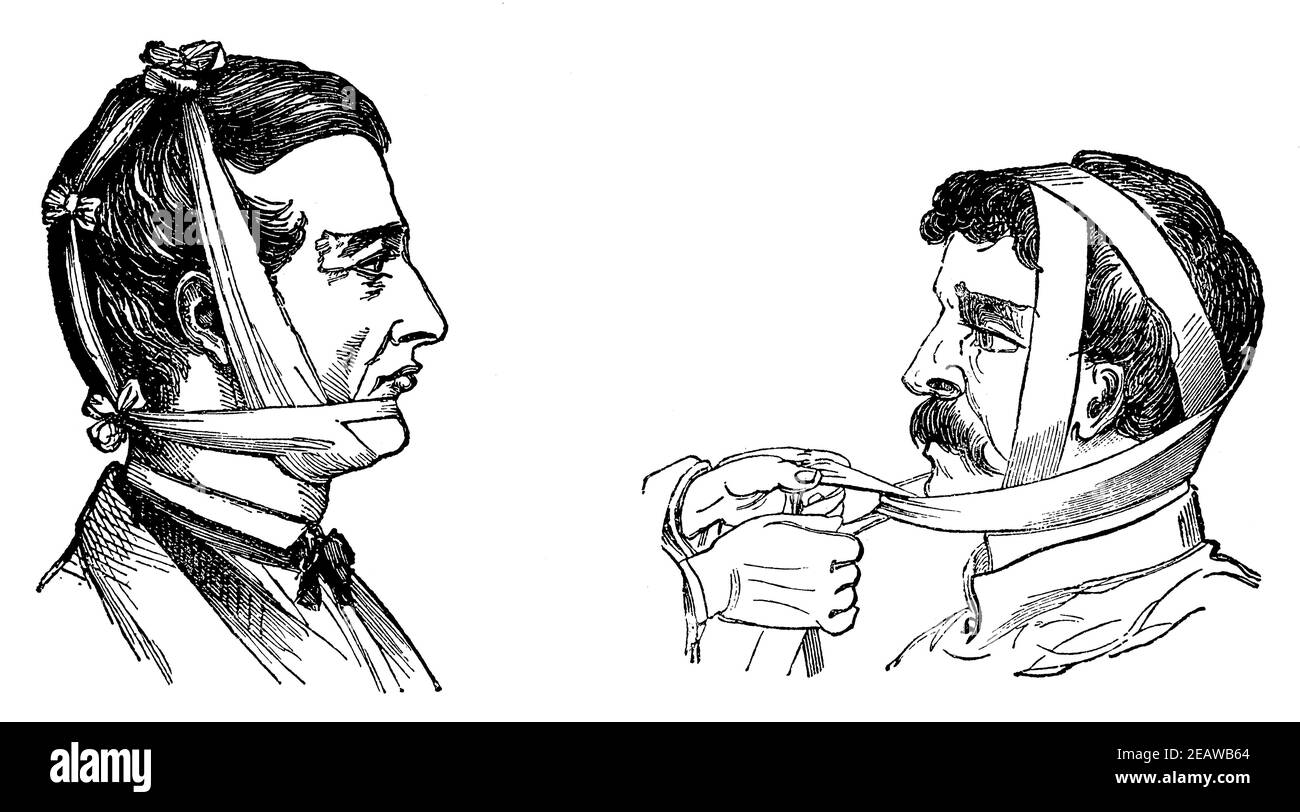

Bandages de la mâchoire inférieure cassée. Illustration du 19e siècle. Allemagne. Arrière-plan blanc. Banque D'Imageshttps://www.alamyimages.fr/image-license-details/?v=1https://www.alamyimages.fr/bandages-de-la-machoire-inferieure-cassee-illustration-du-19e-siecle-allemagne-arriere-plan-blanc-image402542620.html

Bandages de la mâchoire inférieure cassée. Illustration du 19e siècle. Allemagne. Arrière-plan blanc. Banque D'Imageshttps://www.alamyimages.fr/image-license-details/?v=1https://www.alamyimages.fr/bandages-de-la-machoire-inferieure-cassee-illustration-du-19e-siecle-allemagne-arriere-plan-blanc-image402542620.htmlRF2EAWB64–Bandages de la mâchoire inférieure cassée. Illustration du 19e siècle. Allemagne. Arrière-plan blanc.